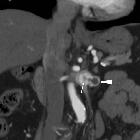

Asymptomatic

left renal vein aneurysm with thrombosis. Multiplanar reformatted images (b..d) from portal venous phase acquisition depicted the lesion (arrowheads) as a saccular outpouching of the left renal vein (*), with internal nonenhancing tissue (thin arrows) representing intraluminal thrombus.